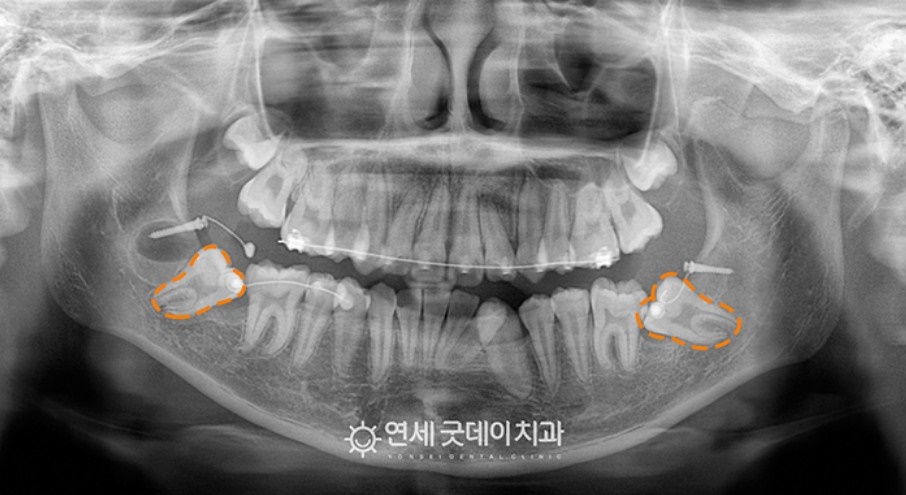

이제 구강외과 전문의 협진을 통해 견인교정하는 과정입니다.

우선 잇몸은 열고 사랑니는 발치한 뒤, 바로 세워야 하는 치아에 나사를 심고 장치를 붙여서 철사로 연결하는 구강외과 수술을 시작했습니다.